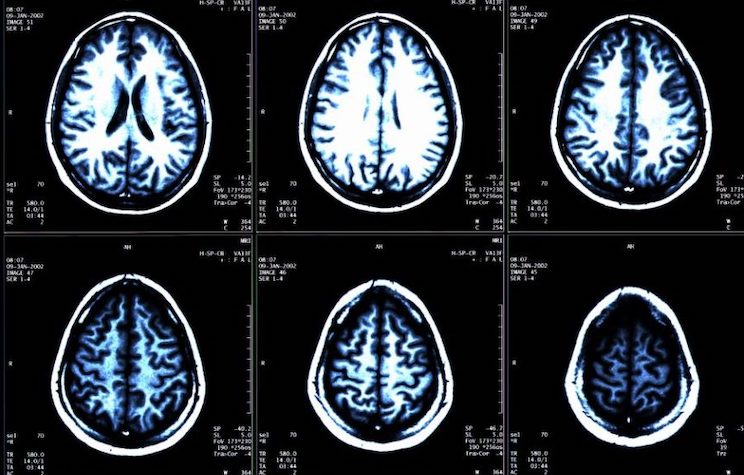

- In another case, a young mother quickly lost nearly 60 pounds, developed insomnia and began hallucinating. Brain imaging showed advanced signs of atrophy.

Using a case description guideline developed by a team of neurologists and epidemiologists, the clinic decides if the patients warrant further investigation or if they may have a known illness or disease. Determining who becomes part of the cluster is subjective, largely because the brain is notoriously difficult to study. Certainty is often only obtained after the patient dies and the cerebral tissue can be fully tested.